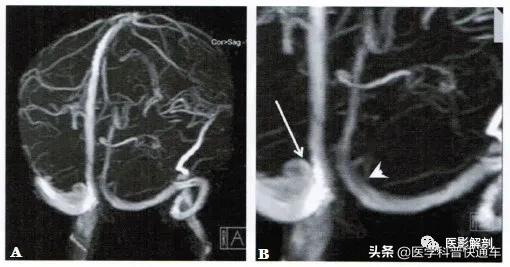

图1 头颅MRV解剖变异

颅内静脉窦TOF法MRV检査。A.斜后位MRV重组图,B. MRV局部放大图。上矢状窦连接右侧横窦(箭),直窦注入左侧横窦(箭头)。左右横窦完全不 相连。

I :上矢状窦连接右侧横窦,根据直窦和左侧横窦连接情况又可分为3种形式:

①直窦连接左侧横窦,左右横窦通过直窦或导管相连;

②直窦连接左侧横窦,左右横窦之间无连接( 图1 );

③直窦连接右侧横窦,左侧横窦未发育。